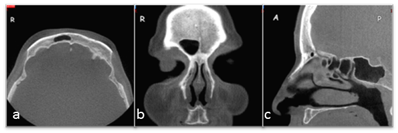

We designed a retrospective study consisting of images of 410 patients (190 male, 220 female; aged 15 to 69 years; mean age, 33 years 7 month ± 13 years 9 month) who presented at our clinic between June 2008 and September 2010. Dental volumetric tomography (NewTom-FP; Quantitative Radiology, Verona, Italy) scanning was performed on patients who were resting in supine positions. Positioning of the patients' heads was performed using two light-beam markers. The vertical positioning light was aligned with the patients' mid-sagittal lines, which helped to keep the head centered with respect to the rotational axis. The lateral positioning light was centered at the level of the sinus, indicating the optimized center of the reconstruction area. In addition, the head position was adjusted in such a way that the hard palate was parallel to the floor, while the sagittal plane was perpendicular to the floor. Dental volumetric tomography DVT scans with 0.5-mm slices in the coronal plane were obtained. Imaging parameters were kV=110, mA=10, and FOV=140 mm. The output was automatically adjusted during a 360º rotation according to tissue density (automatic exposure control system). Two dental radiologists in this study evaluated the DVT images using DVT software (Quantitative Radiology, NNT Software version 2.21, Verona, Italy) with respect to aplasia and agenesis of the frontal sinus on coronal images based on a method proposed by Eggesbø et al. [20]. In this method, frontal sinus aplasia was defined as the absence of frontal bone pneumatization with no ethmoid cells extending above a line tangential to the supraorbital margin. Frontal sinus aplasia was also defined by an oval-shaped sinus with the lateral margin medial to a vertical line drawn through the middle of the orbit (vertical line) with a smooth superior margin and with an absence of the sinus septa (Fig. 1).

Fig 1

Frontal sinus aplasia is defined as the absence of frontal bone pneumatization with no ethmoid cells extending above a line tangential to the supraorbital margin (horizontal line). Frontal sinus aplasia is also defined by an oval-shaped sinus with the lateral margin medial to a vertical line drawn through the middle of the orbit (vertical line) with a smooth superior margin and an absence of the sinus septa [20].